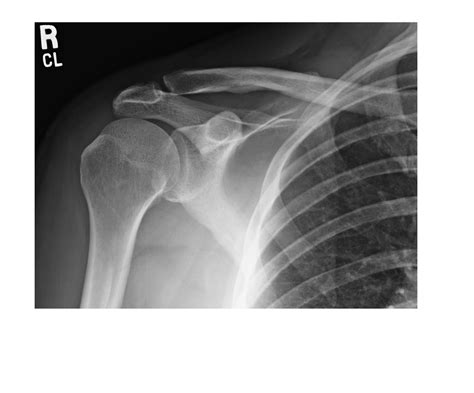

• Dislocations: If the humerus has popped out of the socket, an X-ray confirms the position of the bones and ensures no small fractures occurred during the incident.

Bone Displacement Indicates a dislocation or subluxation event.